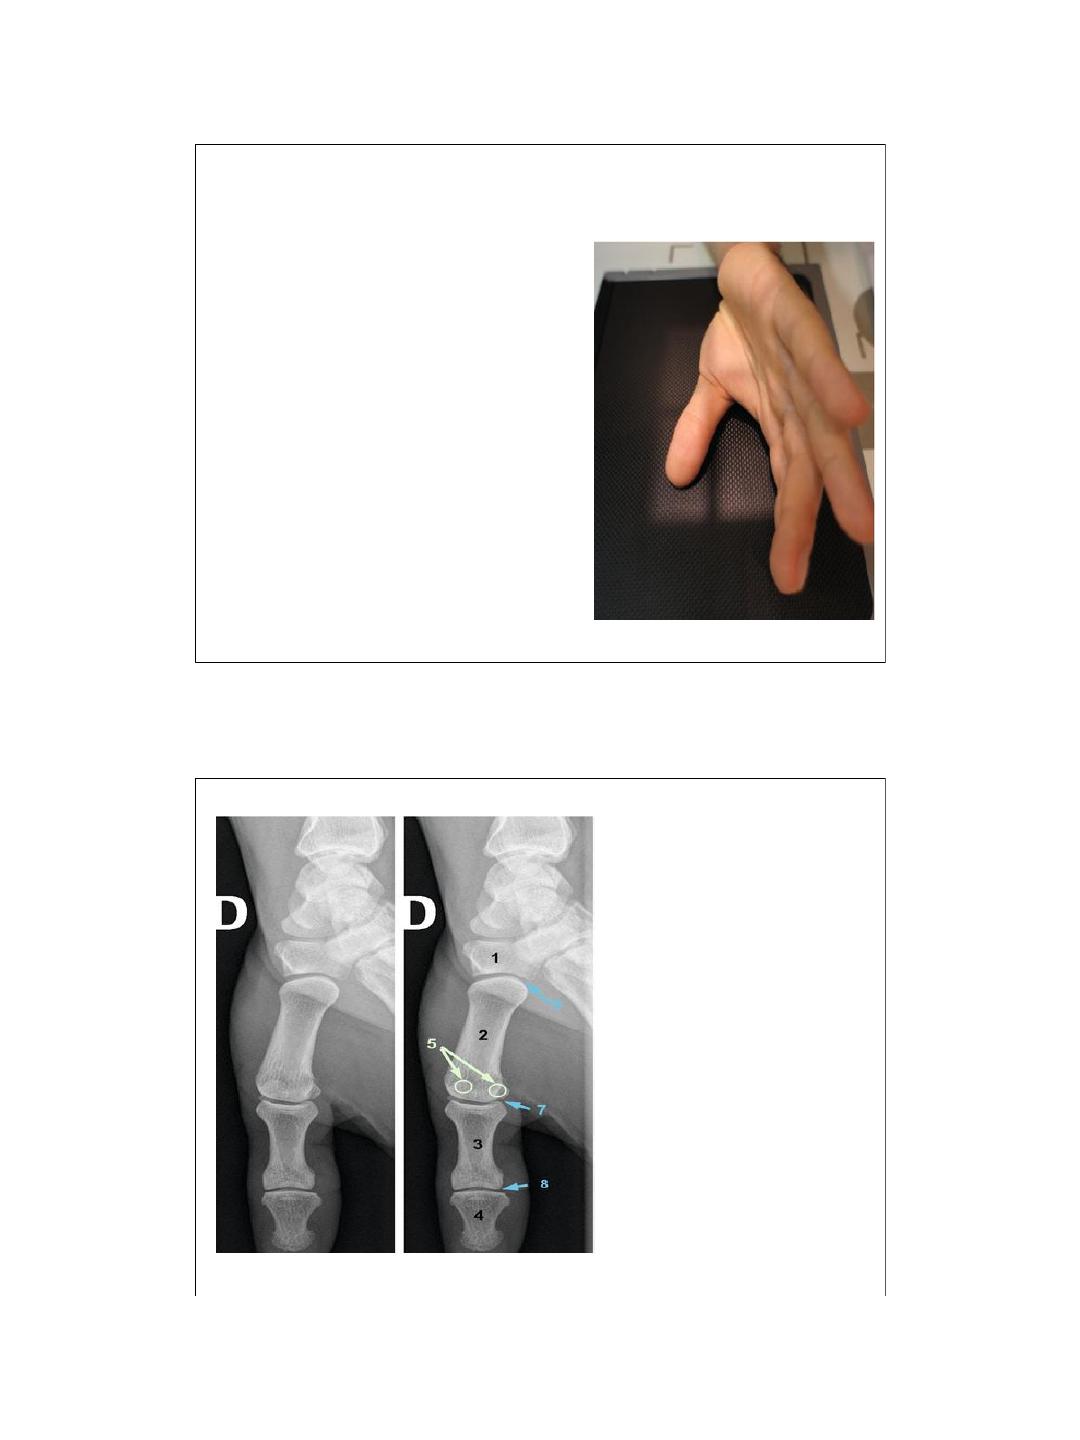

Pouce: Incidence de face palmodorsale

Positionnement

– Assis.

– Membre supérieur en extension et en

hyperpronation.

– Doigts en extension.

Rayon directeur

Vertical.

Centrage

-Pli de flexion proximal du pouce.

Critères de réussite

– Visualisation des articulations

scaphotrapézienneet trapézométacarpienne.

– Métacarpe et phalanges de face en entier.

– Aspect symétrique des sésamoïdes.

I n t é rê t

-Traumatologie, rhumatologie.

1. Trapèze.

2. 1er métacarpien.

3. Phalange proximale.

4. Phalange distale.

5. Sésamoïdes.

6. Articulation

trapézométacarpienne.

7. Articulation

métacarpophalangienne.

8. Articulation

interphalangienne.